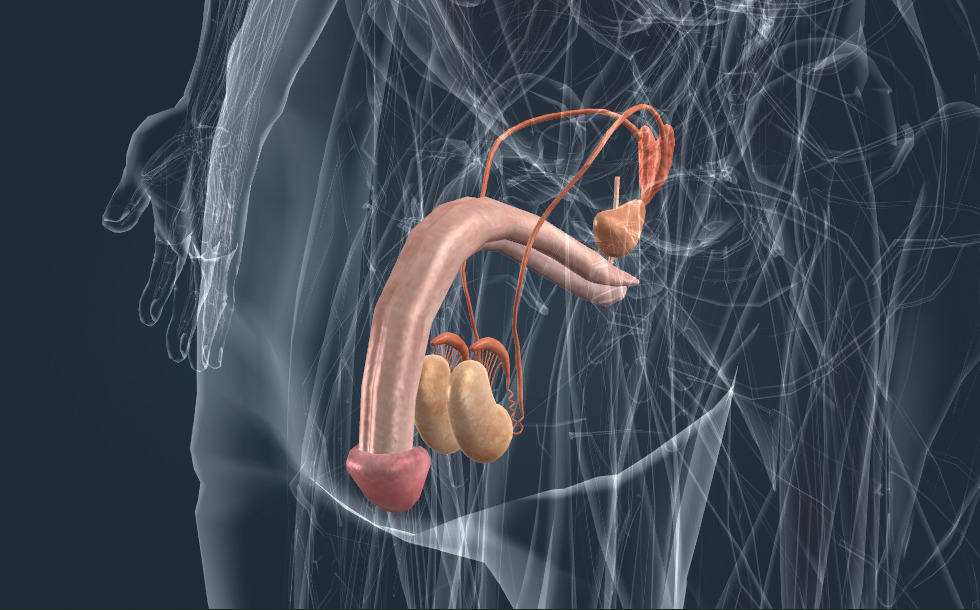

Αναπαραγωγικό σύστημα

- όρχις - Παράγει το σπερματοζωάριο και την τεστοστερόνη (ανδρική φυλετική ορμόνη), η οποία προάγει την ωρίμανση του σπερματοζωαρίου και την ανάπτυξη του ανδρικού σώματος και της τριχοφυίας.

- επιδιδυμίδα - Αποθηκεύει το σπερματοζωάριο που παράγεται στους όρχεις.

- σπερματικός πόρος

- σπερματοδόχος κύστη - Παίζει σημαντικό ρόλο στη δημιουργία του σπέρματος.

- προστάτης - Παίζει σημαντικό ρόλο στη δημιουργία του σπέρματος. Ονομάζεται επίσης προστάτης.

Τα γεννητικά όργανα είναι υπεύθυνα για την αναπαραγωγή, παράγουν γαμέτες. Κατά τη γονιμοποίηση το ωάριο ενώνεται με ένα σπέρμα και σχηματίζει ένα ζυγωτό από το οποίο αναπτύσσεται το έμβρυο. Οι αναπαραγωγικοί αδένες στα αρσενικά είναι οι όρχεις, που παράγουν σπέρμα. Το σπέρμα αποθηκεύεται στην επιδιδυμίδα. Κατά τη διάρκεια της εκσπερμάτωσης αποβάλλεται το σπέρμα μαζί με τους σπόρους ζώου μέσω της ουρήθρας. Το σπέρμα παράγεται από τον προστάτη και τα σπερματοζωάρια.

Τα γεννητικά όργανα είναι υπεύθυνα για την αναπαραγωγή, καθώς παράγουν τους γαμέτες. Κατά τη γονιμοποίηση, ένα ωάριο ενώνεται με ένα σπερματοζωάριο και σχηματίζουν ένα ζυγωτό από το οποίο αναπτύσσεται το έμβρυο. Οι γεννητικοί αδένες στους άνδρες είναι οι όρχεις, οι οποίοι παράγουν τα σπερματοζωάρια. Τα σπερματοζωάρια αποθηκεύονται στην επιδιδυμίδα. Κατά τη διάρκεια της εκσπερμάτωσης, τα σπερματοζωάρια εξέρχονται μαζί με τους σπερματικούς πόρους μέσω της ουρήθρας. Το σπέρμα παράγεται από τον προστάτη και τις σπερματοδόχους κύστεις.

Τα γεννητικά όργανα είναι υπεύθυνα για την αναπαραγωγή, καθώς παράγουν τους γαμέτες. Κατά τη γονιμοποίηση, ένα ωάριο ενώνεται με ένα σπερματοζωάριο και σχηματίζουν ένα ζυγωτό από το οποίο αναπτύσσεται το έμβρυο. Οι γεννητικοί αδένες στους άνδρες είναι οι όρχεις, οι οποίοι παράγουν τα σπερματοζωάρια. Τα σπερματοζωάρια αποθηκεύονται στην επιδιδυμίδα. Κατά τη διάρκεια της εκσπερμάτωσης, τα σπερματοζωάρια εξέρχονται μαζί με τους σπερματικούς πόρους μέσω της ουρήθρας. Το σπέρμα παράγεται από τον προστάτη και τις σπερματοδόχους κύστεις.